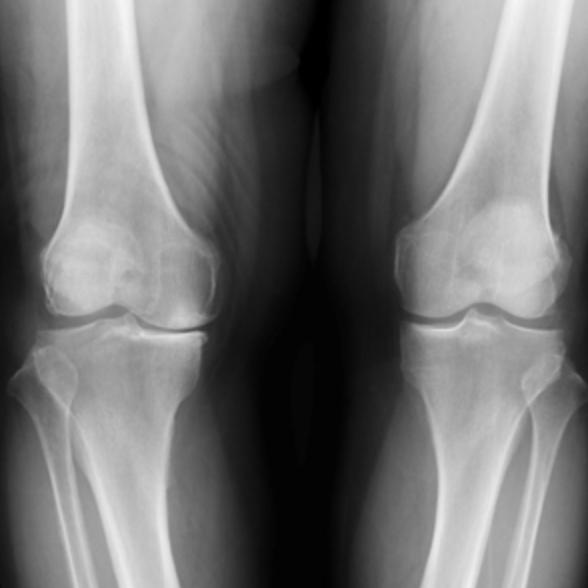

통증으로 병원을 찾았을 때 엑스레이를 찍으면 무릎 사진을 보실 수 있는데요. 위의 허벅지 뼈와 아래의 정강이 뼈 사이에 연골이 닳아 뼈와 뼈가 거의 맞닿아 있는 상태에 가깝다면 수술 상담을 받아보시는 게 좋습니다.